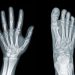

A doctor diagnoses leukemia after doing a physical exam, taking a detailed medical history and ordering lab tests. X-rays, CT scans or MRI scans of your chest and brain can spot signs of leukemia or other tumors. Your doctor may also order a lumbar puncture (spinal tap) to test fluid around your brain and spinal cord. Other tests can show how many blood-forming cells you have and whether they’re healthy. These include a complete blood count, a blood smear, a bone marrow biopsy and a test that looks for genes that can cause certain kinds of leukemia.